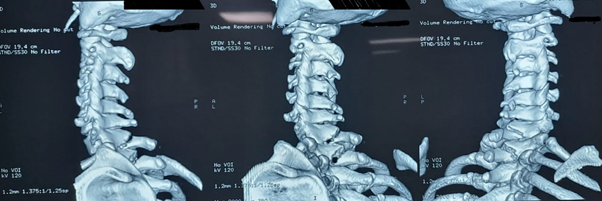

Workup imaging consisted of X-Ray and CT which demonstrated a fracture of the vertebral body of C5 and C6 and the spinous process of C7 (Figure 1). Due to clinical instability of the fractures and risk of neurological compromise, the patient was admitted to the department of neurosurgery. MRI was performed to clear any spinal cord lesion (Figure 2). A posterior cervical fixation guided under fluoroscopy was planned to stabilize the spinal column and prevent potential neurological injuries. Post operatively, analgesics and anti-inflammatory medications were prescribed and physical therapy was recommended to regain cervical function. Follow up demonstrated no neurological compromise, and the patient referred to minimal pain. Cervical rotation was conserved and flexion and extension was restricted (Figure 3).

Figure 1 3D reconstruction revealing the C5 and C6 cervical fracture